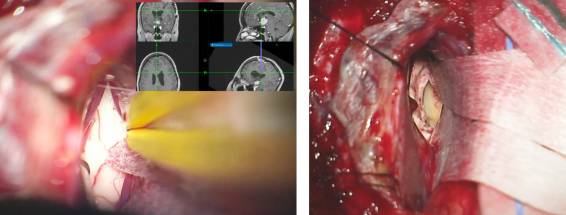

总之,经胼胝体入路显露了同侧脑室。然后,切断隔静脉与丘纹静脉之间的连接扩大Monro孔。这一操作允许通过分离一小段前脉络膜裂而无需处理丘脑和丘纹静脉就可扩大室间孔。两侧不对称的肿瘤可对侧经室间孔入路(交叉对角线)处理其外侧部分。

图9. 神经导航是引导术者通过合理而有限的切开胼胝体(左图),从预期的手术角度到达到室间孔的关键所在。2cm的胼胝体切开恰好位于中线右侧,显露右侧脑室(右图)。在脑室汇聚点释放脑脊液进一步松弛额叶。注意用缝线牵引大脑镰上方适当推移上矢状窦。

图11. 将隔静脉在临近室间孔处汇入丘纹静脉时分离并电凝,然后切断(上图)。下图提供了关于右侧脑室及相关解剖的术中照片。